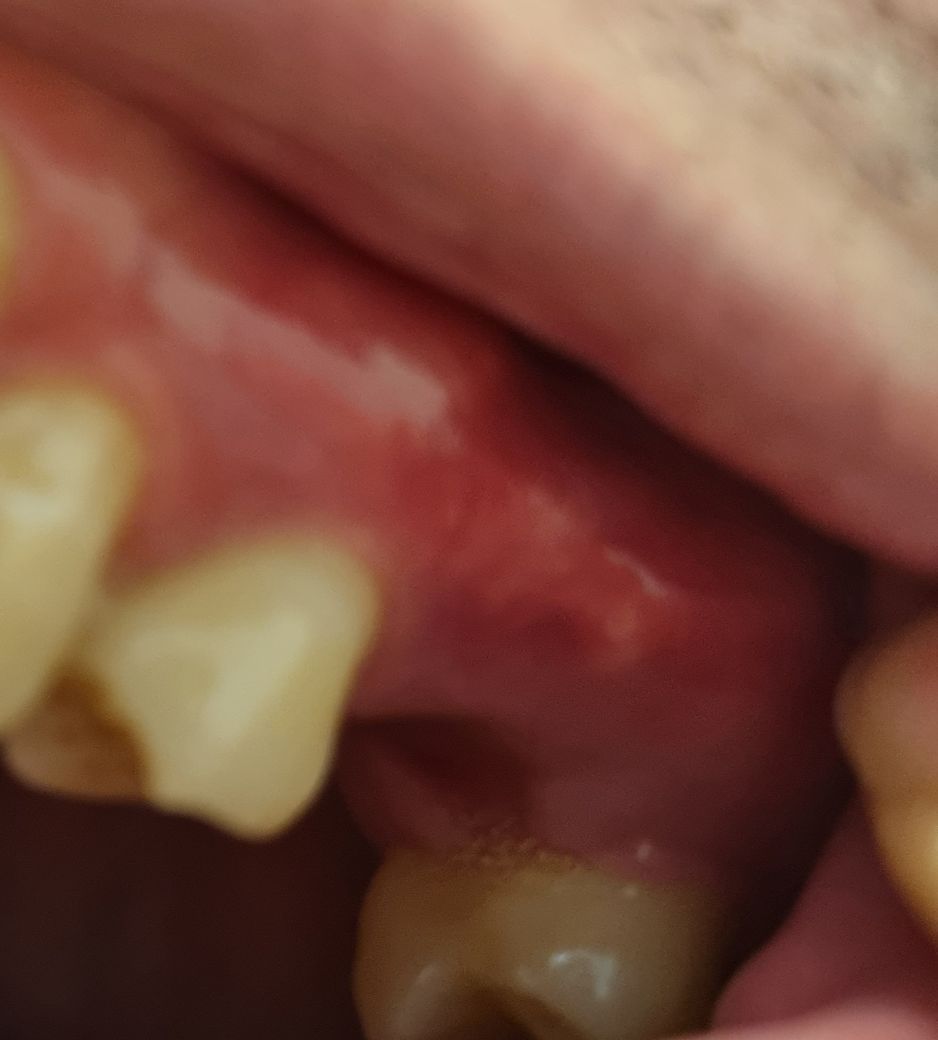

양치하려고 보니 사진과 같이 흰색부분이 뾰족하게 툭 튀어나와있는데 손으로 누르면 뾰족해서 그런지 약간 아픕니다.

사진상에서 보니 심하지 않으니 건드리지 마시고 그냥 두세요.